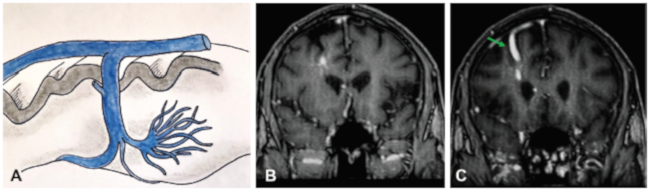

El signo de la cabeza de Medusa corresponde a un hallazgo imagenológico observable en las anomalías venosas del desarrollo (AVD), antes conocidas como angiomas venosos, tanto en tomografía computada (TC) como en resonancia magnética (RM) con contraste endovenoso. Consiste en un ramillete de venas medulares dilatadas que se disponen radialmente alrededor de una vena colectora central, la cual drena al sistema venoso superficial, a una vena ependimaria profunda o a un seno venoso.1,2,3 El signo fue descripto por primera vez angiográficamente en 1967 por Wolf en un paciente con angiomas venosos múltiples, mientras que el primer registro radiológico fue realizado en 1968 por Constans.4 Su nombre proviene de la mitología griega, haciendo referencia a las serpientes que forman el cabello de Medusa, un monstruo que convertía en piedra a aquellos que la miraran fijamente a los ojos (►Figura 1).

La patogenia de las AVD no está del todo clara. Su origen podría asociarse a la ausencia de la vía normal de drenaje venoso de un territorio del cerebro (por ejemplo la hipoplasia o agenesia del 1/3 anterior del seno longitudinal superior) (►Figura 2).4